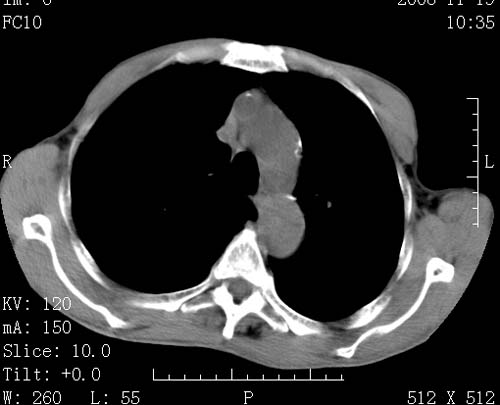

标题: CT16691:m 67 胃镜确诊食管下段及贲门癌 [打印本页]

标题: CT16691:m 67 胃镜确诊食管下段及贲门癌

术前查体,双肺部结节是转移?结核?请点评

转移 隆突下淋巴结亦肿大

首先考虑转移,纵隔内淋巴结亦肿大;

1)符合食管癌表现。2)两肺及纵隔淋巴结多发性转移瘤。3)左肺上叶舌段及两肺下叶炎症感染。

食管癌伴双肺转移,评述:肺部毛细血管网丰富,全身血液均快速流经肺部,癌细胞容易过滤定植,形成转移瘤,影象特点为以毛细血管末梢为中心的结节灶,边缘光滑锐利,少见有中心空洞着,不同来源的转移瘤可有各自特点,如甲状腺癌为双肺弥漫性微结节,本例有原发灶,双肺影象灶典型,左肺舌段条带状网格样伴胸膜天幕征,可视为癌性淋巴管炎。